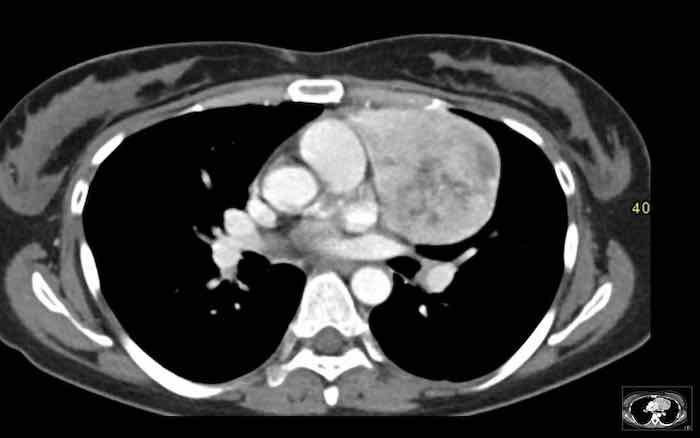

Các hình ảnh này của một nam giới 19 tuổi, được chụp CT để loại trừ thuyên tắc phổi.

Phát hiện tình cờ một khối ở khoang trước mạch máu.

Chẩn đoán có khả năng nhất là tăng sản tuyến ức và MRI được thực hiện để phân biệt thêm khối này.

Trên hình ảnh chuỗi xung T2W, tổn thương có tín hiệu tăng nhẹ.

Trên hình ảnh pha đối (out-of-phase), không có sự sụt giảm tín hiệu đáng kể.

SII nhỏ hơn 9%.

Do bệnh nhân không có bất kỳ triệu chứng nào, đặc biệt không có các triệu chứng có thể liên quan đến u lympho, và vì u tuyến ức (thymoma) là một khối u hiếm gặp, quyết định được đưa ra là theo dõi sau sáu tháng.

Tại thời điểm theo dõi sáu tháng, tuyến ức có hình ảnh bình thường.

Kết luận được đưa ra là đây là tăng sản tuyến ức hoặc mô tuyến ức tồn dư kích thước lớn, đã thoái triển trong vòng sáu tháng.